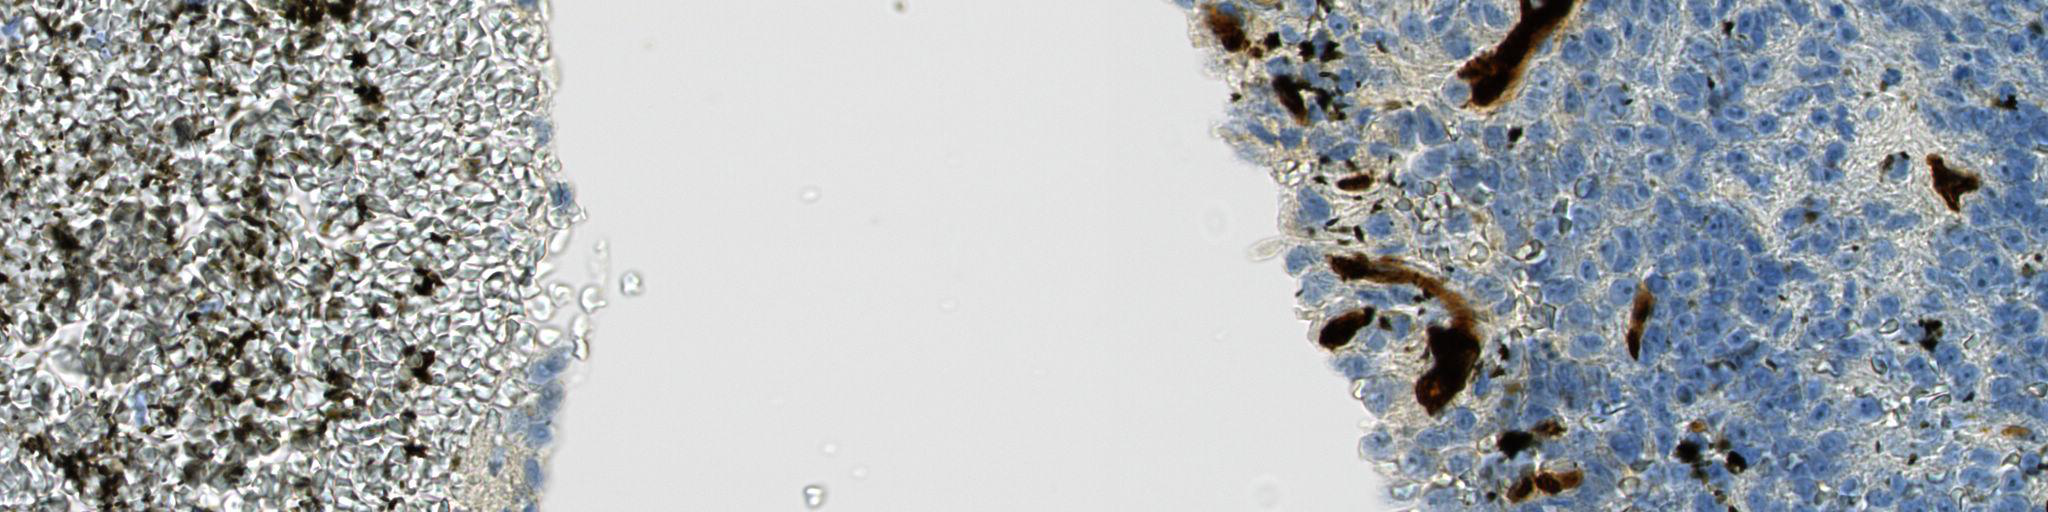

Figure 5 - Example of a segmentation of tissue and vessel walls (detail).

On this excerpt of a WSI at resolution 40×40\times, the final result of the segmentation by our method is shown. The areas considered as sharp tissue are shaded, and the areas inside sharp tissue considered as vessel walls on the basis of the CD34 immunostaining are contoured in cyan. Scale bar = 20 microns.